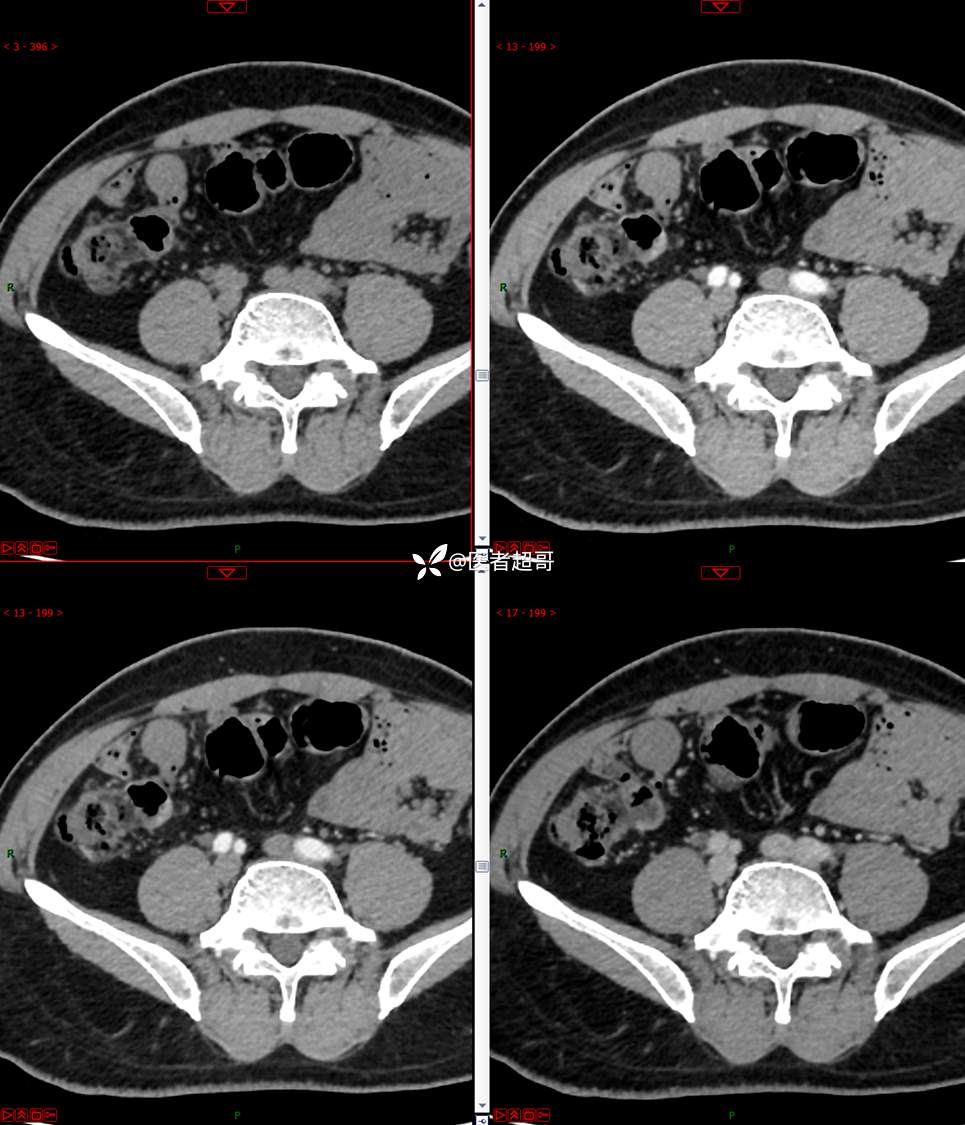

【影诊笔记747】结节不大,挺有意思的,做手术了,请赏析!

男,48岁 0200608 01

主诉:腹痛1月余。

现病史:患者1月余前无明显原因及诱因出现腹痛,脐周为著,为持续性隐痛,无发热,无恶心、呕吐,无腹泻,伴反酸,无胸闷、憋气,无呕血、黑便,至我院门诊就诊,查肝胆胰脾肾彩超诊断:肝胆胰脾双肾未见异常,下腹部实性团块,建议进一步检查,血淀粉酶46U/L,血常规未见明显异常,自服“肠炎宁”药物治疗,效果欠佳,现患者为行进一步治疗,门诊以“腹痛待查 腹腔肿物”收入院。患者自发病以来,神志清,精神可,饮食、睡眠可,大小便正常,体重较前无明显减轻。